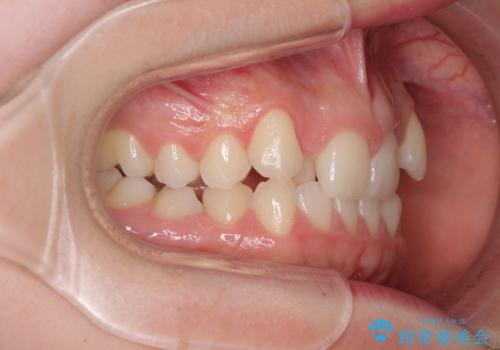

目立つ八重歯を目立たない装置で ハーフリンガルによる抜歯矯正

- ハーフリンガル

- 前歯のデコボコと八重歯を気にして来院された患者様です。

目立たない装置を希望されたので、上顎が裏側装置のハーフリンガルを選択し、左右上顎小臼歯1本ずつを抜歯して、矯正治療を行うこととしました。